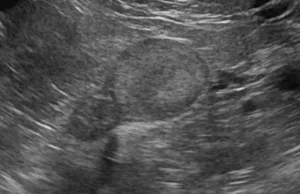

- 超音波検査(心臓、腹部全臓器のスクリーニング検査)